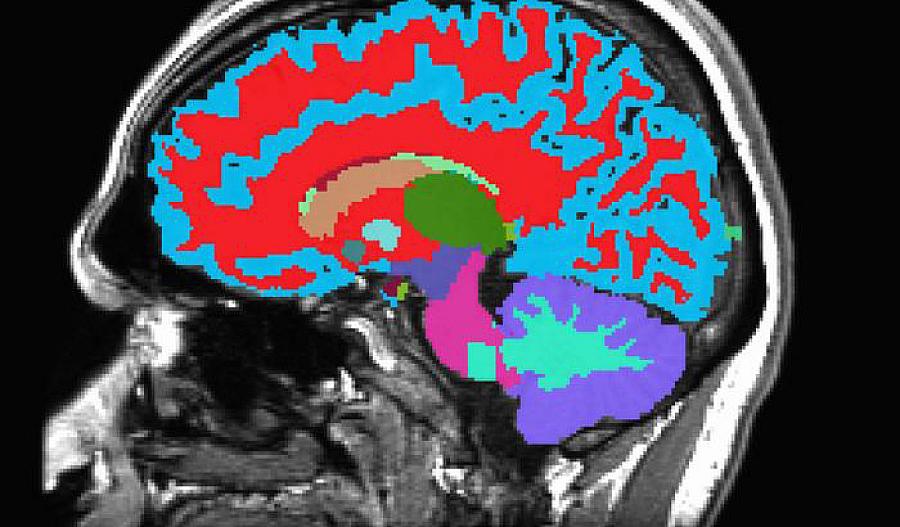

Un estudio reciente de Sullivan y su equipo utilizó imágenes cerebrales para ver cómo el alcohol afecta el cerebro. Descubrieron que los adultos mayores que abusaron del alcohol tuvieron una mayor pérdida de tejido cerebral en comparación con sus compañeros que no bebieron. Esto era cierto incluso si comenzaron a abusar del alcohol de manera tardía.